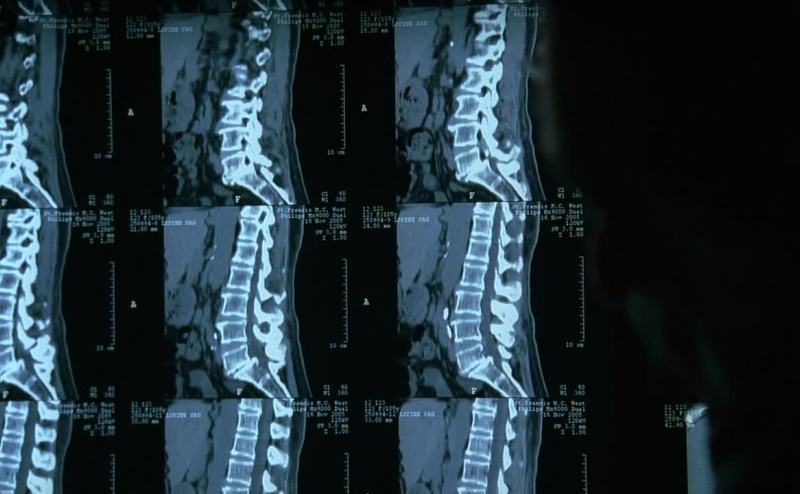

Look here and here.

You can see it's eroding into the spinal artery in the L5 area.

Plus all this extradural growth.

I'm surprised it hasn't caused permanent ischemia.